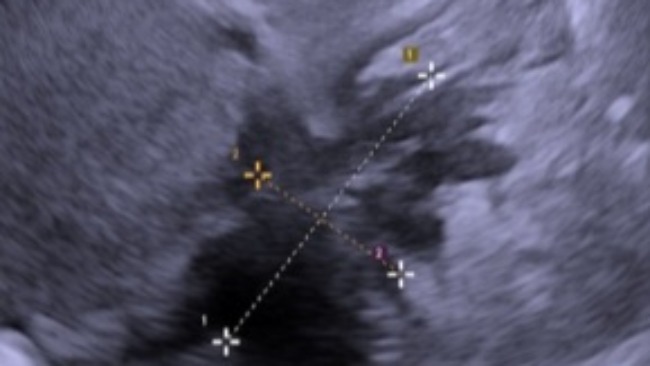

Cześć mam na imię Paulina i mam 27 lat. W roku 2020 roku zdiagnozowano u mnie ENDOMETRIOZE GŁĘBOKO NACIEKAJĄCĄ objawy endometriozy zaczeły sie pokazywać w roku 2016 lecz nikt nie sądził, że to akurat będzie to ZŁO jak ja to nazywam.

Aktualnie jestem na środkach farmakologicznych i po 2 zabiegach usunięcia 2 ognisk lecz jest tak już zaawansowana że kwalifikuje się do usunięcia laparoskopowego niestety operacja jest kosztowna koszt operacji to od 15-25 tysięcy w zależności od kliniki